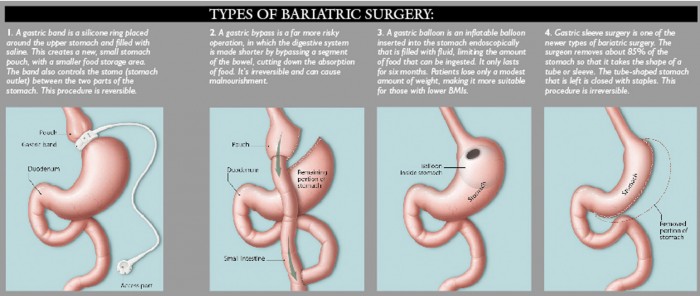

9 Bariatric surgeries/Gastric yypass:

Surgeons suffer a harder time in service and must employ particular instruments as internal organs are usually hard to divide. These patients also suffer an increased risk for difficulties with anesthesia, as it is often complicated to put in the tube inside their airways. Breathing must be strongly checked before, throughout and after the surgery, as patients are more expected to be exposed to an advanced risk of increasing of pneumonia.